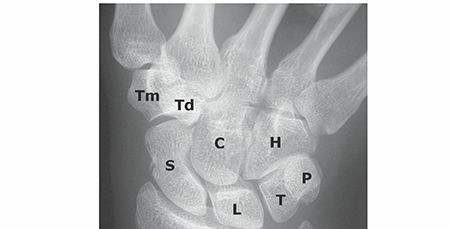

WRIST INJURIES EPIDEMIOLOGY The annual incidence of carpal fractures in the United States was reported at mor…